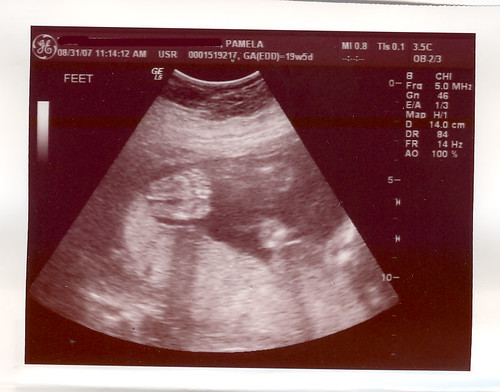

Feet!

Sorry about the news. 😦 There are indeed many little ones who do just fine and I think your most excellent, beautiful bone structure gives them plenty of room. (I was thinking how totally screwed I would be if I had twins or trips!) Those itty bitty feet are precious! Very cool that you will have 3 boys/3 girls. Hopefully girls so El and Em can share clothes. 🙂 I think you need a diff doc if you are dissatisfied with him. There are other docs and you shouldn’t have to feel neglected or discouraged. These are your BABIES and you deserve the best care from someone who truly cares and you and your pregnancy. Then set off a poop bomb or something on evil doc’s doorstep. 🙂